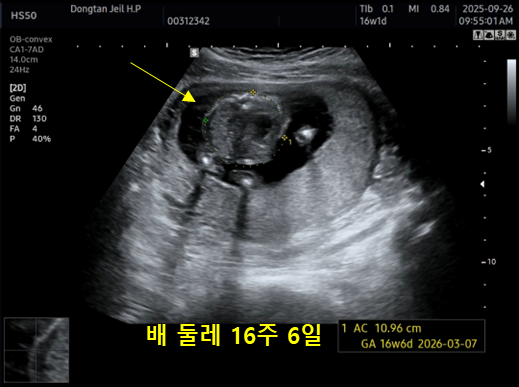

| 복부 AC | 10.96 cm | 16주 6일 | 배 둘레 |

전체적으로 주수와 거의 비슷하게 성장하고 있어서 크게 벗어난 부분이 없다고 하셨어요.

머리는 16주 2일, 배는 16주 6일로 조금 더 크게 나왔고, 허벅지는 15주 6일 정도로 살짝 작게 찍혔는데, 의사 선생님께서 “범위 안에 다 정상”이라고 말씀해 주셔서 안심했답니다.